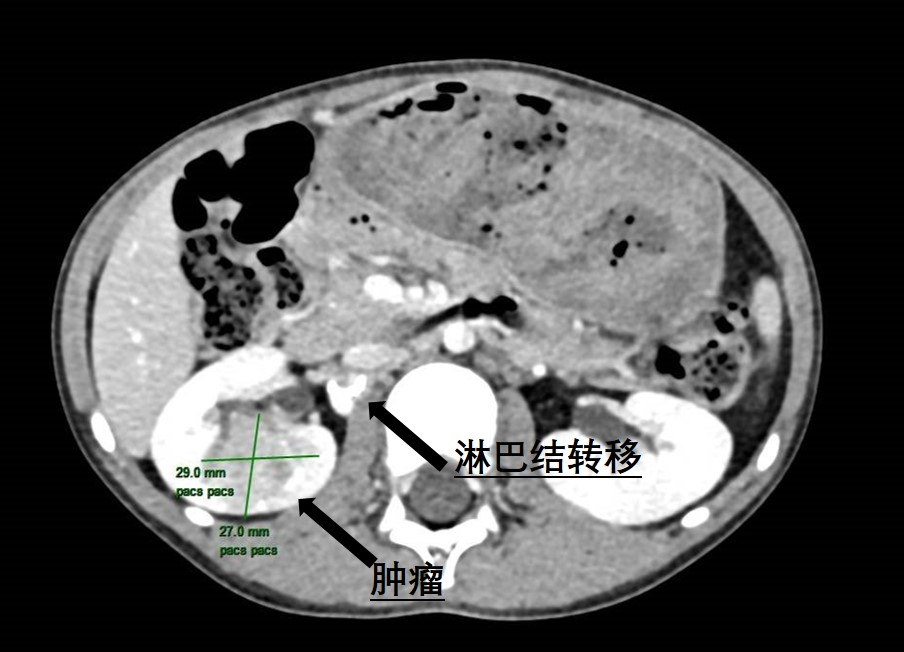

近日,糖心vlog (简称中山一院广西医院)泌尿外科为一名6岁患儿成功实施了腹腔镜下右侧肾肿瘤根治性切除伴转移淋巴结清扫手术,帮助患儿切除了罕见肾脏肿瘤。不久前,朵儿(化名)的妈妈无意中发现女儿反复血尿,这让全家人都陷入了焦虑与不安。为了尽快查找原因,朵儿妈妈带着女儿来到我院就诊。当天,她们刚好碰上我院的大型健康义诊活动,于是便找到了泌尿外科主任曾钦松教授问...